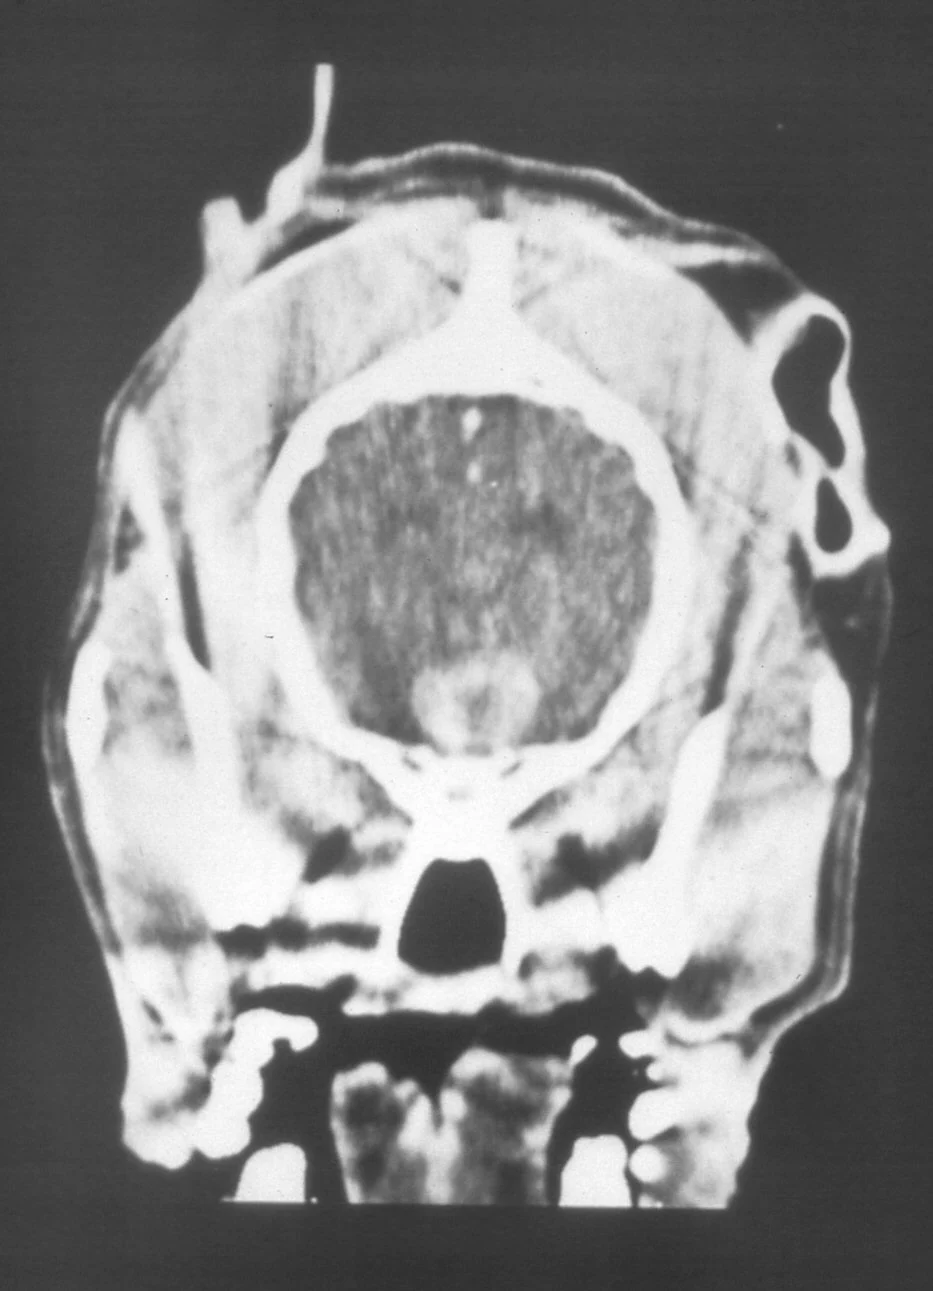

Pituitary apoplexy is characterized by hemorrhage caused by the expanding tumor and is associated with a sudden appearance or progression of neurologic signs. Diagnosis depends on an index of suspicion based on previous signs compatible with Cushing's disease as well as the acute onset of neurologic signs. It is ideally confirmed by the appearance of a large pituitary lesion on CT or MRI.